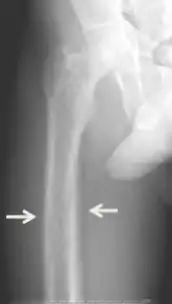

Diagnosis includes both clinical and laboratory investigations. Radiological investigations include looking for signs of bone loss in both the hands and pelvis which is characteristic of tertiary hyperparathyroidism.[8] Other clinical examination can include grading of muscle weakness, which is done by asking the patient to stand from a seated position with their hands folded across their chest.[4][8] Laboratory investigations include evaluating blood calcium and alkaline phosphatase, which are always increased in tertiary hyperparathyroidism. Other common results from laboratory investigations would include decreased vitamin D levels, elevated blood parathyroid hormone and hyperphosphatemia.[9][8][1][4]

Parathyroid hyperplasia low mag.